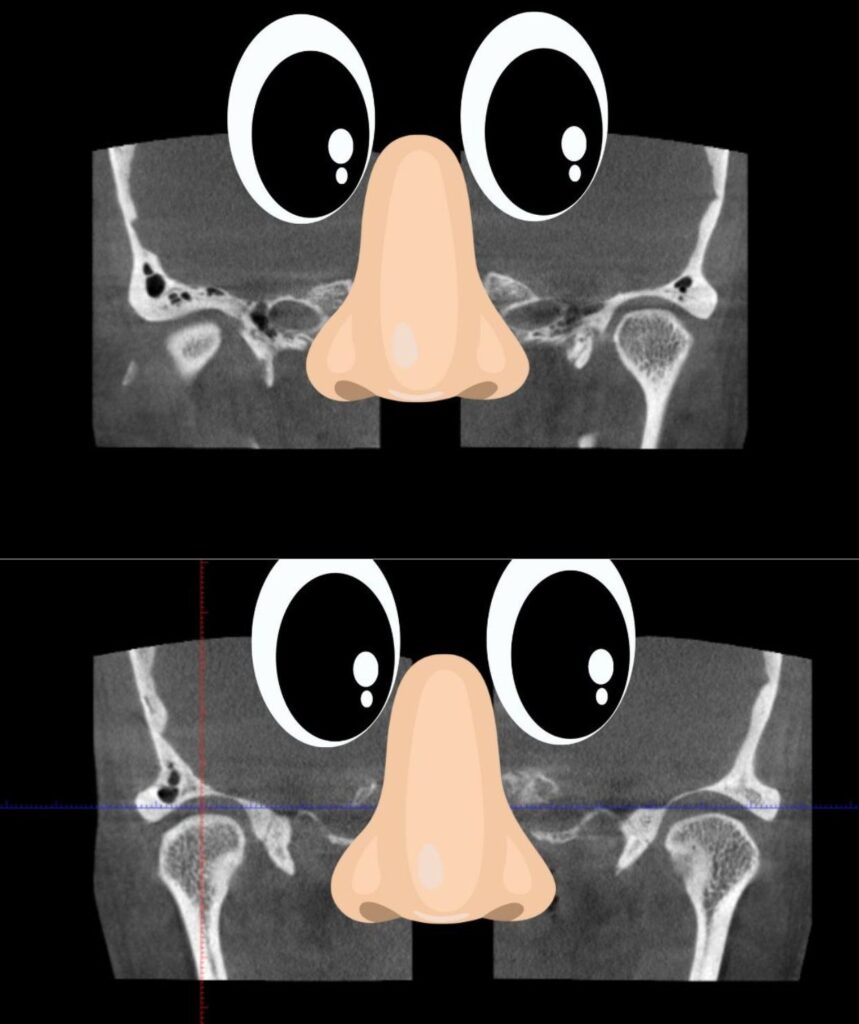

こちらスタート時の顎の関節のCTスキャンです。

こちらの見方はこのようになります。

正面から見た状態となるので目と鼻はこの位置です。

右の関節が左に比べると見えていないことがわかるかと思います。

これは顎がまっすぐでない証拠。

これを今回の顎矯正のマウスピース治療でこうなりました。

両側くっきり均等に映っています。

つまり顎の歪みはとれたということ!

目と鼻を入れますので上の治療前と比べてみてください。

両顎、関節がくっきりはっきりでしょ?

顎の歪みがなくなった証拠です。